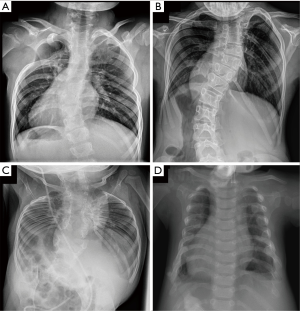

Apart from complication rates being comparable to other distraction-based systems, additional problems that were hoped to be avoided with spine-sparing implants have nevertheless occurred. In a retrospective international multicentre study, a radiographic analysis focusing on extraspinal ossifications of 65 VEPTR patients with a minimum follow-up of 4 years was performed (18). Ossifications were classified as type I (at the anchor points), type II (along the central part of the VEPTR), or type III (re-ossification after thoracostomy). It was reported that 65% of patients showed ossifications, most of them being type I and/or type II (Figure 3). The possible negative impact on chest wall compliance and spinal mobility, especially in type II ossifications, was mentioned but not further investigated.